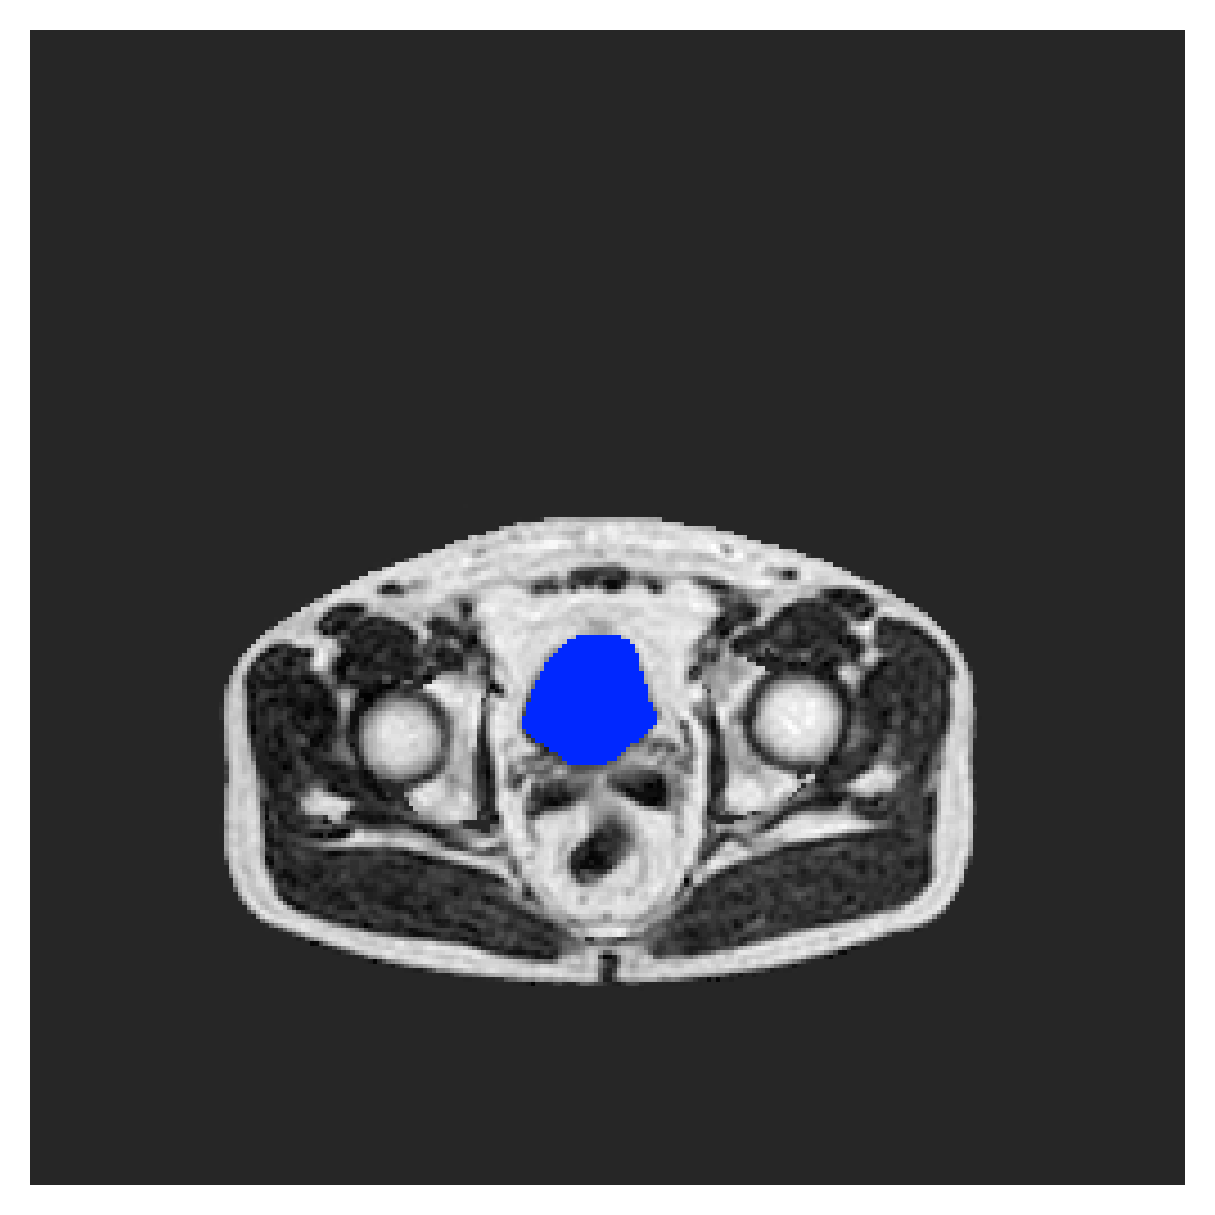

We normalize the volumes and resize the slices to pixels. As the official dataset comes with full annotations, we create a synthetic point ground truth. This is done by first randomly choosing the centers of the point annotations within the class masks, followed by filling an ellipse with axes lengths of and (in pixels) around each center. The intersections of these elliptic discs with the underlying full annotations are then used as our point ground truth. See Figure 2 for an example of the created weak annotation mask. The point annotations are created for every slice, one for each foreground object present in the slice.

The images contain two channels, one for water and one for fat content. For training, we normalize the volumes (per channel) and use 2D slices in the coronal plane, sized . The weak annotations are created synthetically, following the same procedure as described for the ACDC dataset.